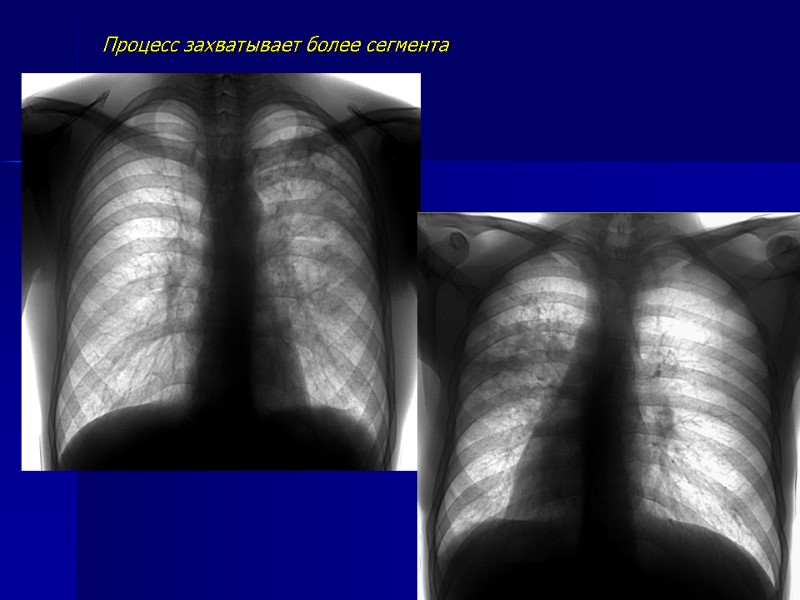

Процесс захватывает более сегмента

Поражена нижняя доля